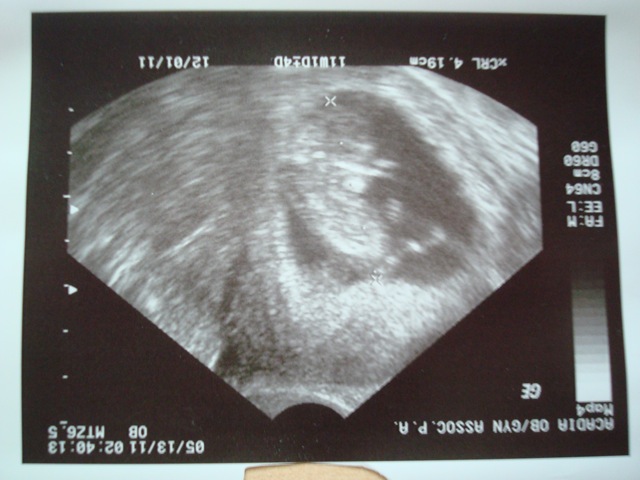

I am still just hanging about being pregnant. I have been very anxious these past couple weeks because my first ultrasound is this Friday. I am dying to see that everything is ok with the baby and that it is growing well. I will be almost 11 weeks along which is 1 week shy of being in my second trimester! That is a long wait, especially since we found out early at 3 weeks.

I am feeling good, just tired, and I have no reason to worry about the health of the baby. I guess it is just the not knowing whats going on in there. Since I have little morning sickness I have no big signs of being pregnant. Truthfully I feel like everything is fine but sometimes I worry that I have it too easy. So I guess I am holding my breath until Friday, think of me and send positive vibes my way around 3:30pm!!

I will post ultrasound pics as soon as I can!